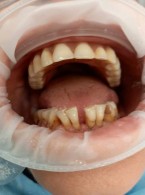

Do mojego gabinetu zgłosiła się 29-letnia kobieta ze zmianami erozyjnymi szkliwa. W wywiadzie pacjentka podała, że od dłuższego czasu przestrzega restrykcyjnej, niskokalorycznej diety i intensywnie uprawia sport. Czy lekarz dentysta może wysnuć podejrzenie anoreksji? Jakie objawy stomatologiczne mogą towarzyszyć temu schorzeniu?